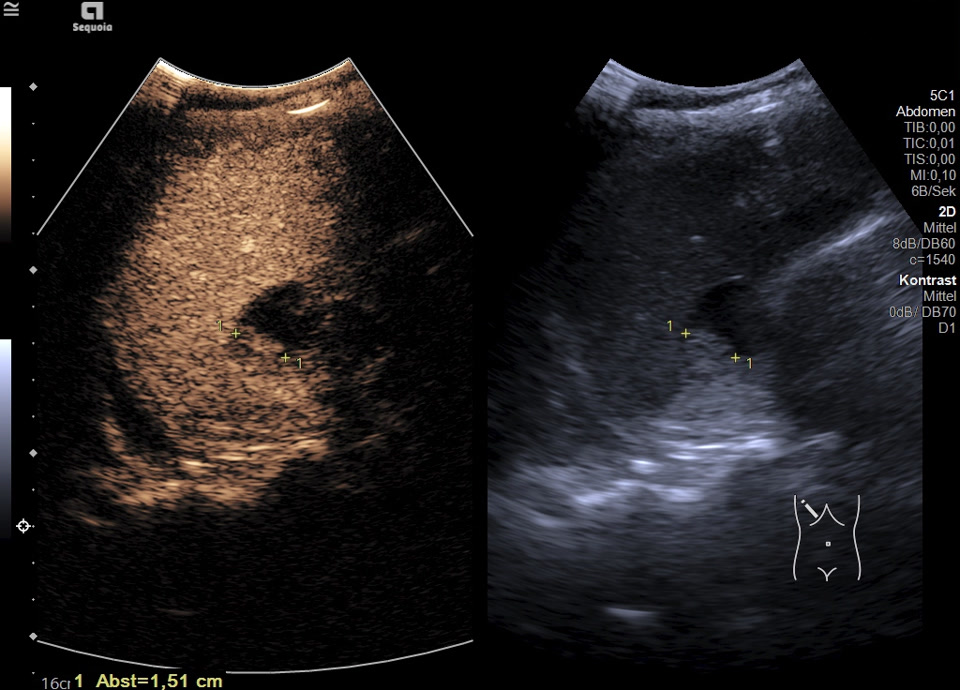

Es zeigt sich subkapsulär in Segment VI der Leber eine zystische Raumforderung mit durchgehendem Kapselreflex und hyperechogenem solidem Anteil. Der Befund ist nicht vereinbar mit einer blanden Zyste, sondern suspekt auf eine zystisch-solide Metastase. In der ergänzenden CEUS nehmen die soliden Anteile in der arteriellen Phase Kontrastmittel auf und zeigen in den portalvenösen sowie späten Phasen eine persistierende KM-Anreicherung ohne Washout. Zusätzlich finden sich eine noduläre Peritonealverdickung im Oberbauch sowie ein zystischer Ovarialtumor mit soliden Anteilen im rechten Unterbauch. In Zusammenschau der Befunde besteht der dringende Verdacht auf ein hepatisch und peritoneal metastasierendes Ovarialkarzinom.